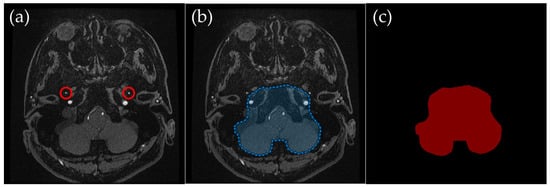

2.3.1. Basal Ganglia Level: Preserving Intracranial Vessels and Removing External Carotid Arteries

Basal Ganglia Level (Figure 2): The external carotid artery branches and other extracranial tissues were excluded, leaving only the brain parenchyma and relevant intracranial vessels. The external carotid artery is particularly problematic in lateral projections, where it can overlap with middle cerebral artery branches, complicating MIP interpretation. This exclusion was crucial to ensuring clear visualization of the middle cerebral arteries in MIP images.

Figure 2. Example of manually annotated training data at the basal ganglia level. (a) Original TOF-MRA axial image (red circles indicate the superficial temporal artery). (b) Manually defined region of interest (ROI) in blue, excluding the external carotid artery and non-intracranial structures. (c) Corresponding indexPNG mask for semantic segmentation training.